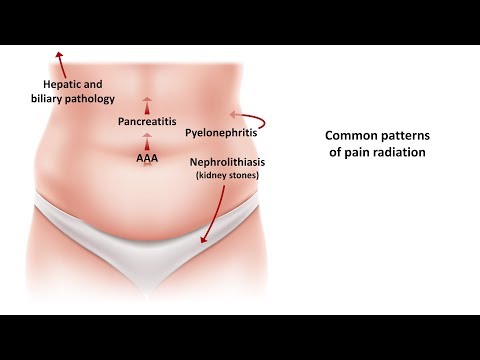

Abdominal Pain Differential Diagnosis

This video highlights different causes of abdominal pain according to the site of the pain in the abdomen. This is the first in a series of #shorts describing different causes of abdominal pain. DISCLAIMER: This or associated videos are not meant for self-diagnosis or a means of avoiding qualified medical care. Strictly for information only.

Differential Diagnosis of Abdominal Pain

Abdominal pain radiating to back? Can you think of other differential diagnoses?